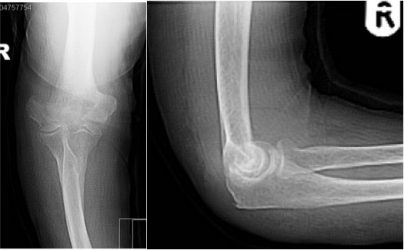

Distal humerus fracture in a 90 year old lady